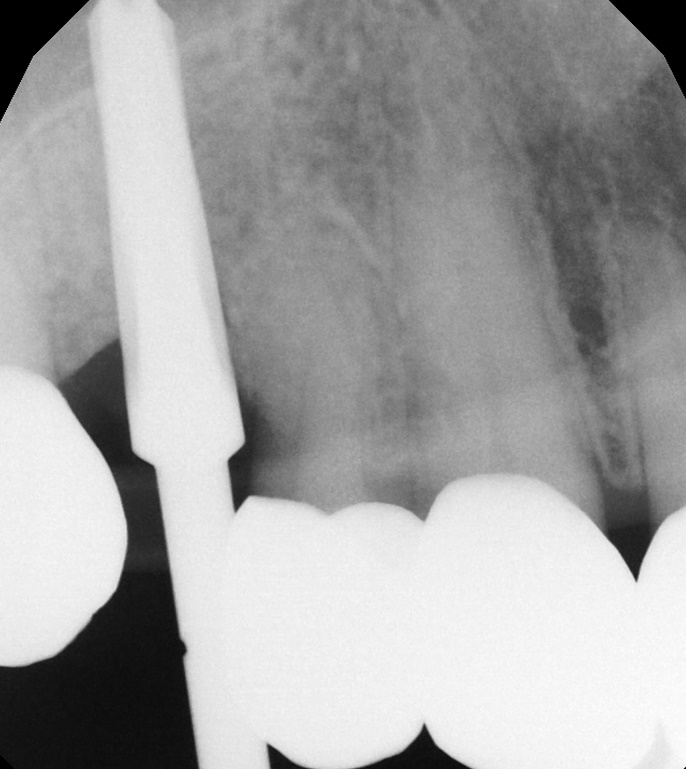

Classic Implant surgery integration in a short time